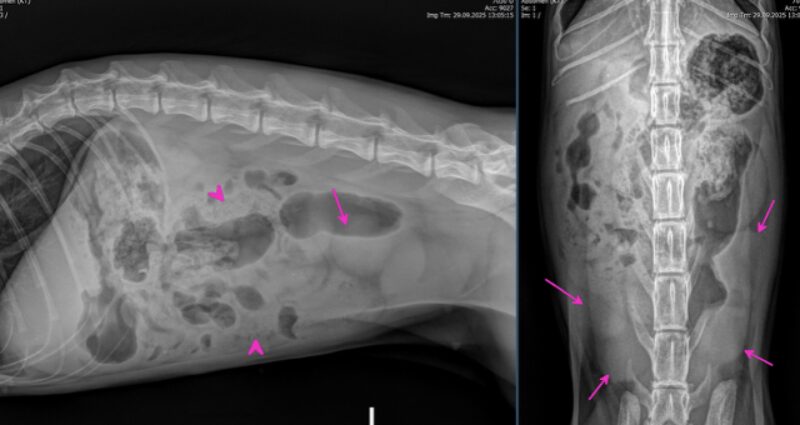

Besten Dank für die Übermittlung dieses spannenden Falles! Es liegen Röntgenbilder des Thorax und des Abdomens in 2 Ebenen vor (sinistro-dextraler Strahlengang, sowie ventro-dorsaler Strahlengang). Wesentliche Hauptbefunde sind im Bereich des muskuloskelettalen Systems, als auch im Abdomen zu vermerken.

Mehrfrageant-Fraktur am rechten Acetabulum. Zum einen besteht am rechten Acetabulum eine Mehrfrageant-Fraktur mit sicherer Beteiligung des Iliums (grüne Rechtecke). Die rechte Darmbeinschaufel ist nach mediokaudal rotiert, wodurch der Beckenkanal kranial des Acetabulums erweitert erscheint. Zusätzlich besteht eine kaudale, sowie minimal dorsale Verschiebung der Darmbeinschaufel, wodurch in der ventro-dorsalen Aufnahme der Trochanter major überlagert wird. Kranio-lateral des rechten Aceatbulums sind mindestens zwei längliche, teils scharfrandige, teils geringgradig irreguläre Knochenfragmente erkennbar (grüne Pfeile). Das Acetabulum selbst ist, soweit beurteilbar, artikuliert mit dem Femurkopf. Eine Beteiligung des rechten Os pubis kann aufgrund der Überlagerung nicht ausgeschlossen werden. Der Gelenkspalt ist jedoch gering- bis mittelgradig erweitert (grüner Pfeilkopf).

Iliosakrale Gelenksluxation: Linksseitig besteht zudem eine iliosakrale Gelenksluxation, wodurch das Becken nach kranioventral verschoben ist und eine geringgradige linksseitige latero-kaudale Rotation entsteht (gelbe Pfeile). Das rechte Iliosakralgelenk ist fraglich subluxiert.

Transversale Fraktur: Eine transversale, minimal irreguläre, vollständige Fraktur ist am lateralen Aspekt des linken Os pubis erkennbar (blaue Pfeile). Diese resultiert in keiner nennenswerten Knochendeviation. Am kaudolateralen Rand des linken Acetabulums befinden sich multiple kleine Fragmente (blaues Rechteck). Im umliegenden Weichteilgewebe ist weder freies Gas erkennbar, noch besteht eine deutliche Weichteilschwellung.

Verwachsene Wirbelkörper: Der S1 Wirbelkörper ist unvollständig mit dem Wirbelkörper des S2 verwachsen (orangener Pfeil). Bilateral besteht jedoch eine Artikulationsfläche beider Ala ossis sacri.

Auffallend im Abdomenröntgen sind runde, homogene, weichteildichte Strukturen, die um die Harnblase lokalisiert sind und sich etwa auf Höhe von L5, sowie L6-7 (pinke Pfeile) befinden. Ihre Ausdehnung entspricht in etwa der Länge eines lumbalen Wirbelkörpers. Im kranialen Abdomen ist das seröse Detail zudem etwas reduziert. Im gesamten Verdauungstrakt findet sich weichteildichtes, teils auch mineraldichtes, granuliertes Material, begleitet von einer moderaten Menge an Luft (exemplarisch mit pinken Pfeilköpfen markiert). Freies abdominales Gas ist nicht nachweisbar und die Harnblase stellt sich intakt dar.

Zusammenfassend ist hervorzuheben, dass es sich bei den weichteildichten Strukturen im kaudalen Abdomen sehr wahrscheinlich um multiple Fruchtblasen in beiden Uterushörnern handelt und somit der hochgradige Verdacht einer Trächtigkeit im Raum steht. Dies sollte unbedingt alsbald ultrasonographisch abgeklärt werden.

Weiters zeigt sich eine subakute, geschlossene, traumatische intraartikuläre Fraktur des rechten Acetabulums mit Beteiligung des rechten Os ilium und potentieller Beteiligung des Os pubis. Das Hüftgelenk bleibt zwar in Artikulation, weist jedoch eine Laxizität und potenzielle Instabilität auf, was auf eine eingeschränkte Belastbarkeit der rechten Hintergliedmaße schließen lässt.

Begleitend besteht eine linksseitige Sakroiliakalluxation mit kranioventraler Verschiebung des Beckens und Rotation nach links latero-kaudal. Rechts ist das SI-Gelenk fraglich subluxiert. Trotz dieser Verschiebungen ist keine signifikante Verengung des Beckenkanals erkennbar, was das Risiko einer funktionellen Obstipation oder Kompression der Beckenorgane aktuell als eher gering erscheinen lässt. Am linken Os pubis besteht zudem eine Fraktur ohne relevante Knochendeviation, während am linken Acetabulum mehrere kleine Fragmente erkennbar sind. Diese sind am ehesten als Chip-Frakturen zu interpretieren; Avulsionsfrakturen oder frakturierte Osteophyten/Gelenkmäuse können jedoch differentialdiagnostisch nicht ausgeschlossen werden.

Zusätzlich zeigt sich ein S1-Übergangswirbel mit beidseitig ausgebildeten Artikulationsflächen der Ala ossis sacri, was als anatomische Variante zu werten ist und vermutlich ohne klinische Relevanz bleibt. Es besteht kein Hinweis auf freie Luft oder eine Blasenruptur. Abschließend geht der Rat zu einer Reposition der rechtsseitigen Ileum-Frakturversorgung sowie der Versorgung der linksseitigen SI-Luxation mit vorheriger Trächtigkeitsabklärung.